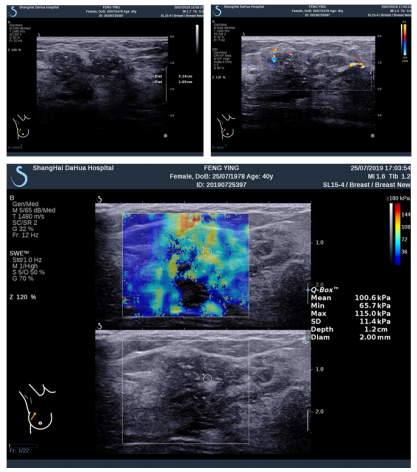

图 2 1 例 44 岁女性经超声引导活检及手术切除诊断为浸润性导管癌

注:a,超见右乳外上象限非肿块型病变,范围 31mm×10mm, BI-RADS 评 级 为 4B;b,2. 彩 色 多 普 勒 超 声 显 示 分 枝 状 彩 色 血 流,RI:0.72;c,SWE 图 像 显 示:Emean:100.6KPa,Emax: 115.0KPa。